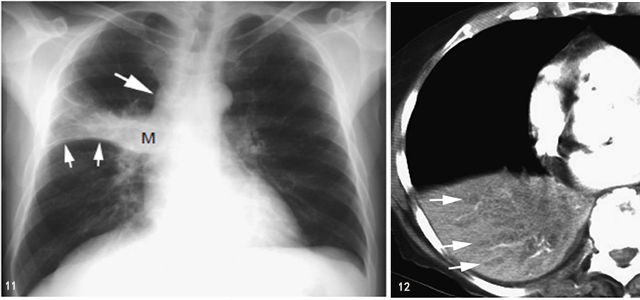

肺不张常见,可累及段、叶或一侧肺(图11),还可继发肺炎或肺脓肿。

图11 鳞状细胞癌伴支气管阻塞和肺不张

胸片显示右肺门大肿块(M) 伴水平裂向上弯曲移位(小箭头)。呈反“S”征,可见纵隔淋巴结增大(大箭头)

阻塞性肺炎是肺癌支气管阻塞的常见表现,在胸片上,常见肺实变和肺容积减少。在CT 上,常见表现包括肿瘤阻塞支气管、肺实变、实变肺内扩张支气管充盈黏液或液体(黏液支气管征),尤其是在对比增强时表现更明显(图12)。通常无空气支气管征。空气支气管征偶见于伴不张和实变的部分阻塞的中心支气管病变。CT 可见肺或肿块内坏死区。

图12 阻塞性肺炎伴黏液支气管征

右肺门癌患者,右肺下叶实变伴体积减小,为阻塞性肺炎典型表现,实变内见黏液支气管征(箭头)